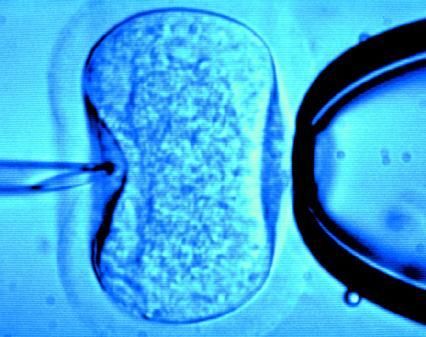

試管嬰兒是指分別將卵子與精子取出后,置于試管內(nèi)使其受精(資料圖)